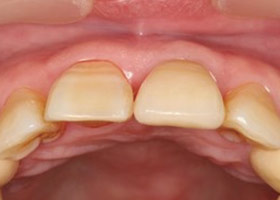

治療前門牙特寫、切端特寫照,發現假牙略微暴牙。

假牙完成後,門牙特寫、切端特寫照,暴牙已不復見。